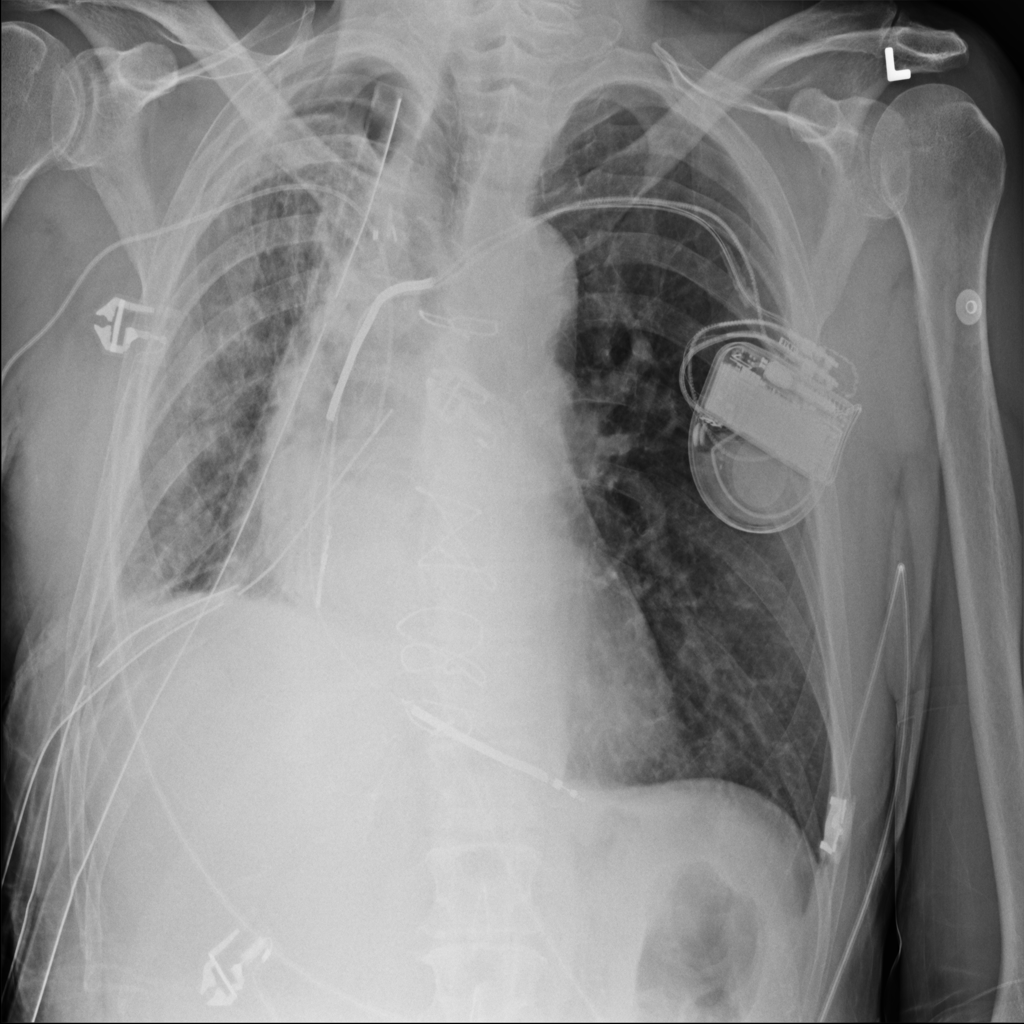

PAT-4639 · IMG-020Pneumothorax

PAT-4639 · IMG-020

PA